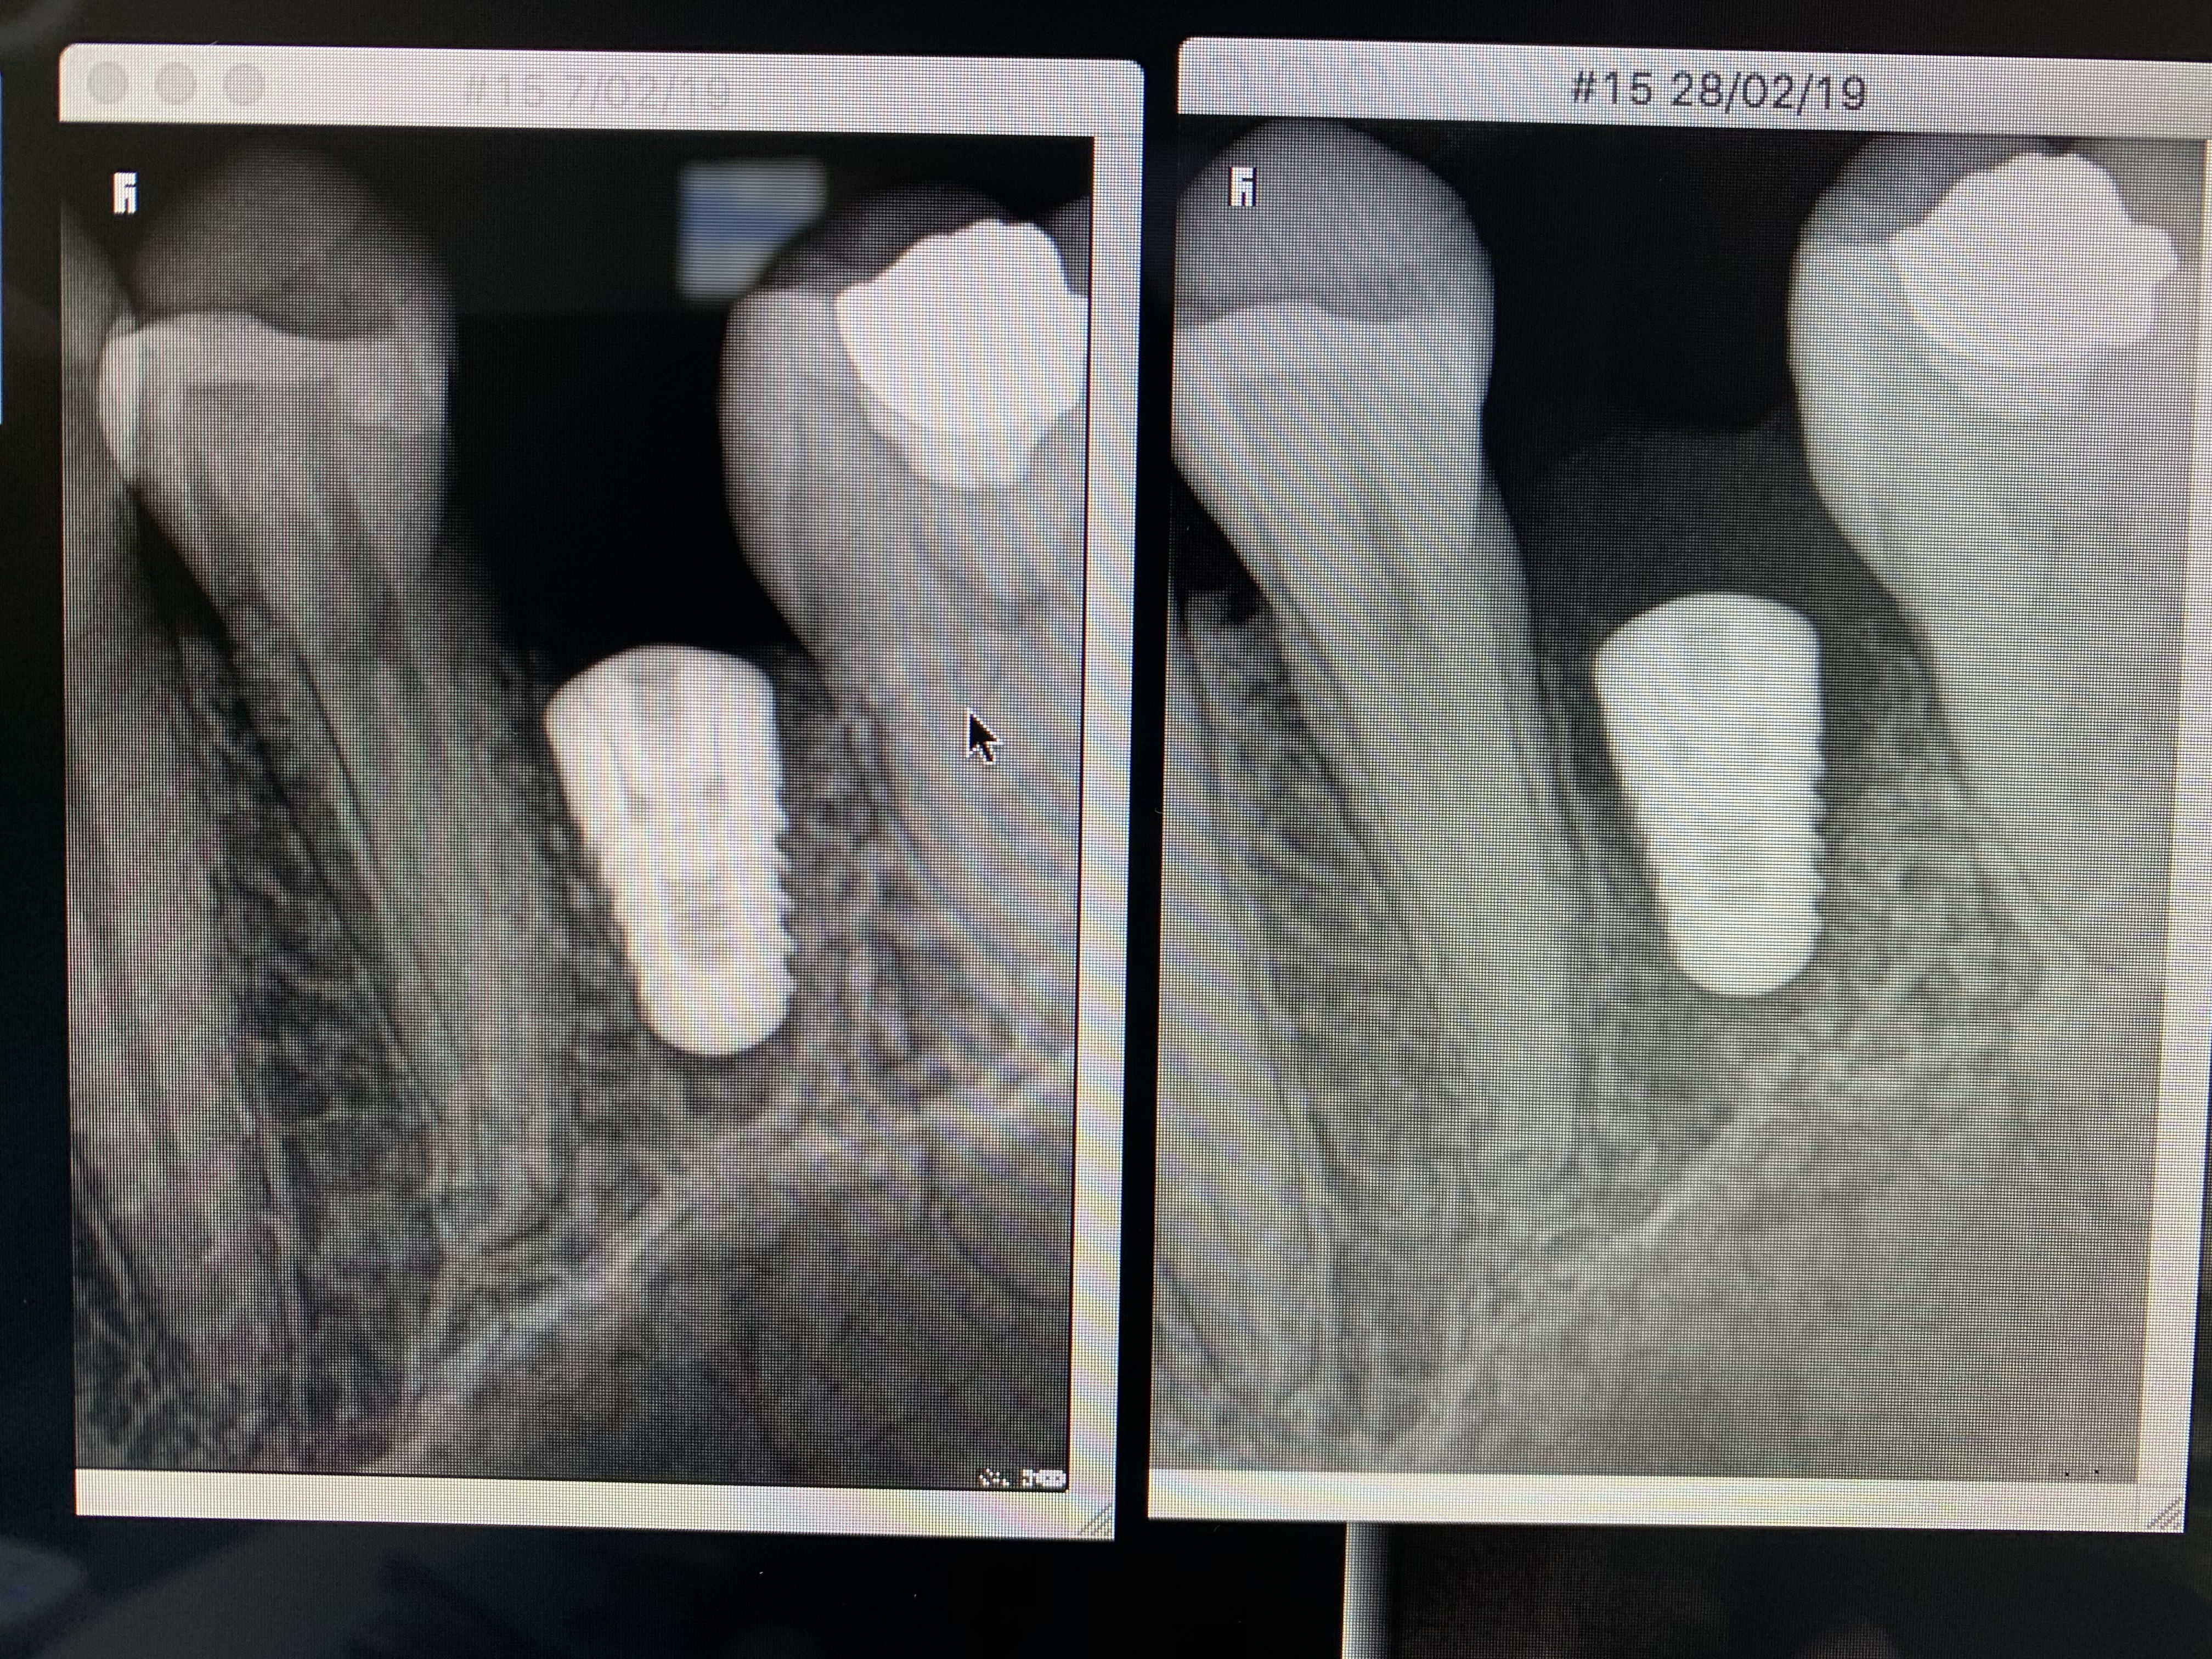

As tu une radio?

Si l’écoulement est purulent, associé à des douleurs, une perte osseuse visible à la radio et/ou d’autres signes cliniques, je serai pour déposer l’implant de suite.

Merci ...oui l’implant est enfoui. L’ecoulement est jaune claire limpide. La gencive a eut du mal a se refermer et aujourd hui on voit une espece de manchon gingival mou dessus. Aucune douleur. Legere perte osseuse mais pas en hauteur. C est plutot le Long de l’implant que j’observe un petit espace noir... a ton avis. Si je depose, je repose combien de temps apres et avec quel protocole ?

Peux tu nous montrer la RVG?

Bon, voilà le résultat : j’ai ouvert et j’ai perdu toute la paroi vestibulaire. L’implant était mobile j’ai déposé et cureté...

Je ne comprends pas ce qu’il s’est passé. Je vous mets des photos. Je suis désolé je ne maîtrise pas trop l’outil informatique pour faire autrement mais elles sont aussi nettes que ce que j’ai à l’écran

Implant trop gros (quel diamètre?)

et court non?

+1 implant trop gros, peut-être une fracture ou ischémie du pan vestibulaire

Ton implant est trop gros et pas assez long

Un 4/10 aurait été bien plus adapté

Tu as dû avoir une ischemie de la paroi vestibulaire